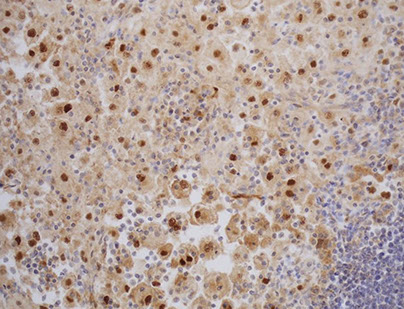

Histiocytic and dendritic cell neoplasms

Hemophagocytic Lymphohistiocytosis, Rosai-Dorfman disease (see Spleen and Lymph Node)

Histiocytic sarcoma

Tumors derived from Langerhans cells

- Langerhans cell histiocytosis (LCH)

- Langerhans cell sarcoma (LCS)

Indeterminate dendritic cell tumor

Interdigitating dendritic cell sarcoma

Follicular dendritic cell sarcoma

- Inflammatory pseudotumour-like follicular/fibroblastic dendritic cell sarcoma

Fibroblastic reticular cell tumor

Disseminated juvenile xanthogranuloma

Erdheim-Chester disease